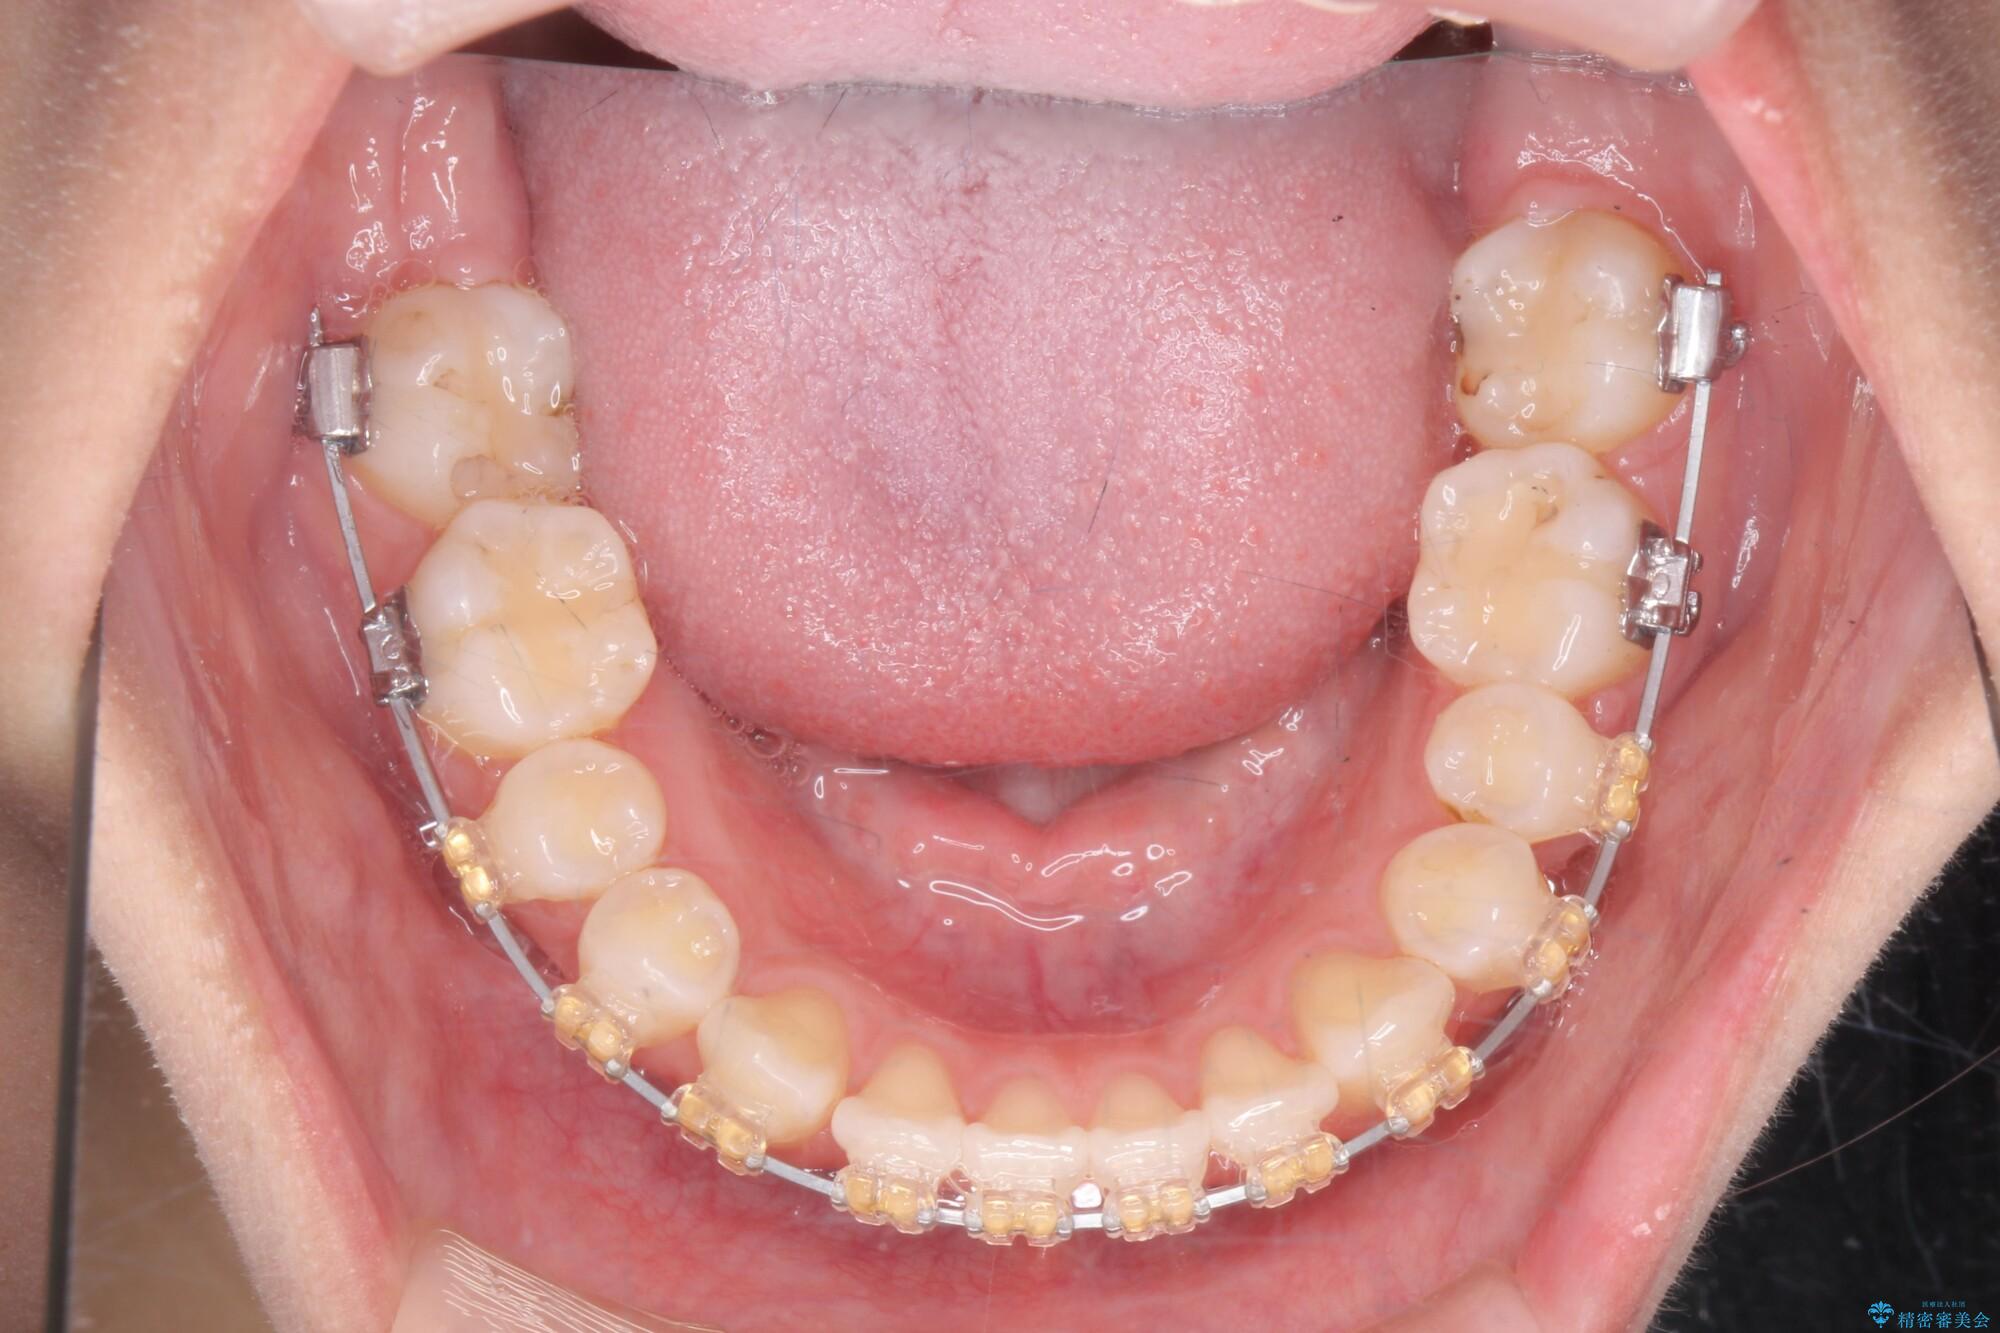

マルチブラケットを用いた非抜歯のワイヤー矯正で噛み合わせと歯並びを改善していきます。

1年で歯並び、嚙み合わせともにしっかりと改善されました。